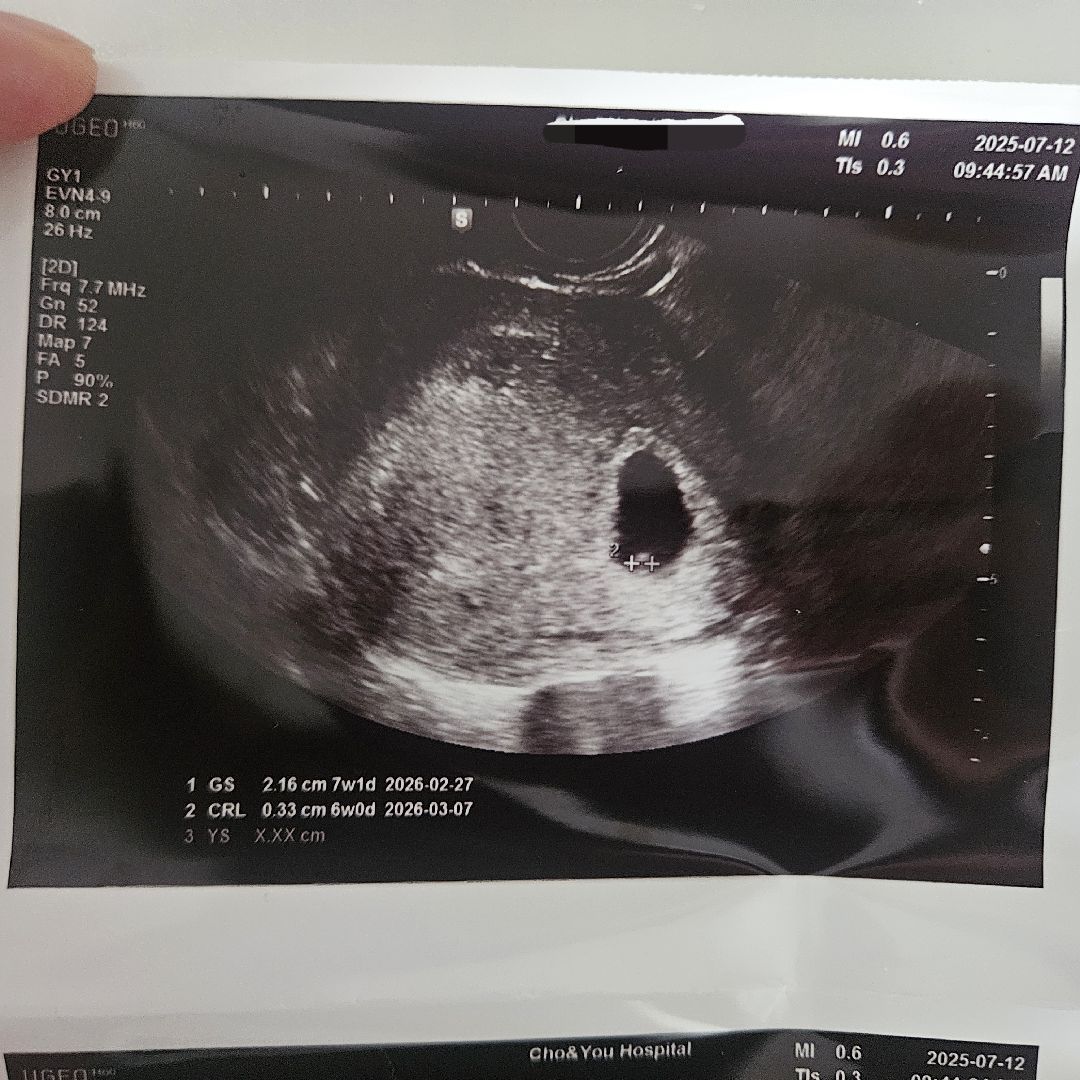

2주 전에 서브병원에서 아기집 확인(5주2일) 후 2주 뒤에 심장소리 들을 수 있다고 해서 오늘 분만병원으로 심장소리를 확인하러 갔어요. 그런데 아기집은 잘 크고 있는데 아기가 확실하지 않아서 일주일 뒤에 다시 오라고 하셨어요. 사진에 표시해주신게 아기인 것 같지만 정확하게 안보인다라고 하시더라구요. 제가 봤을 땐 난황도 안보이는 것 같아요..ㅠ 저랑 비슷했던 분들이 계신가요?

난황같아요! 저도 6주5일까지 다이아도 아닌 작은 난황 외 아무것도 안보였는데 지금 7주5일차에 아기보였어요ㅜㅜ주차와 맞지 않아서 걱정했는데 보통 8-9주쯤 되어야 출산예정일 확정된다고 하더라고요

밑에 측정한 게 난황 아니예요? 아기가 너무 작아서 잘 안 보일 수 있지만 시간 지나면 금방 클 수 있으니 다음 진료 때까지 더 기다려보세요^-^